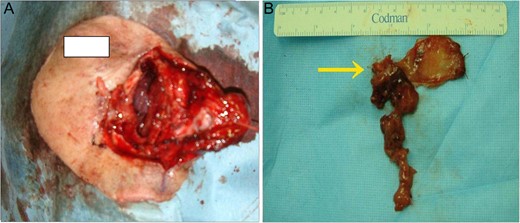

Endoscopic view of the right nasal cavity. (A) Before and (B) after rIL-2 administration. After rIL-2 administration, the tumor size was reduced (arrow).

An extranasal approach (lateral rhinotomy) was performed under general anesthesia. To obtain good visualization, the anterior wall of the right frontal sinus was also opened. The tumor had a pedicle on the right nasal septum near the olfactory cleft, which we extirpated totally, leaving an adequate free margin (Fig. 3A and B). The thick mucous recognized in the ethmoidal sinus proved to be non-malignant.

(A) After wide surgical excision (B) gross specimen. The tumor with a pedicle on the right nasal septum near the olfactory cleft was extirpated totally, leaving an adequate free margin. (arrow: pedicle of tumor).